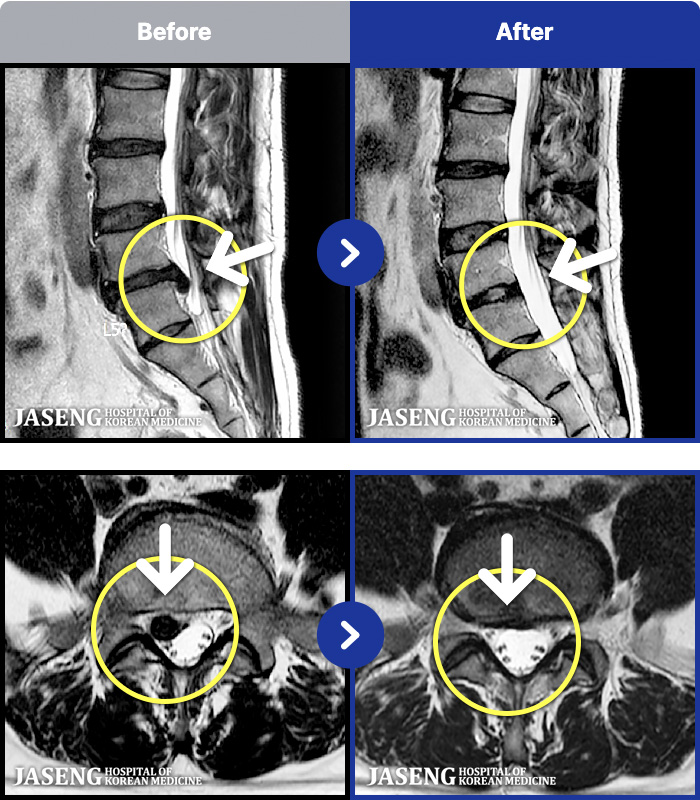

MRI ġ

MRI ũ ʸ Ȯϼ.